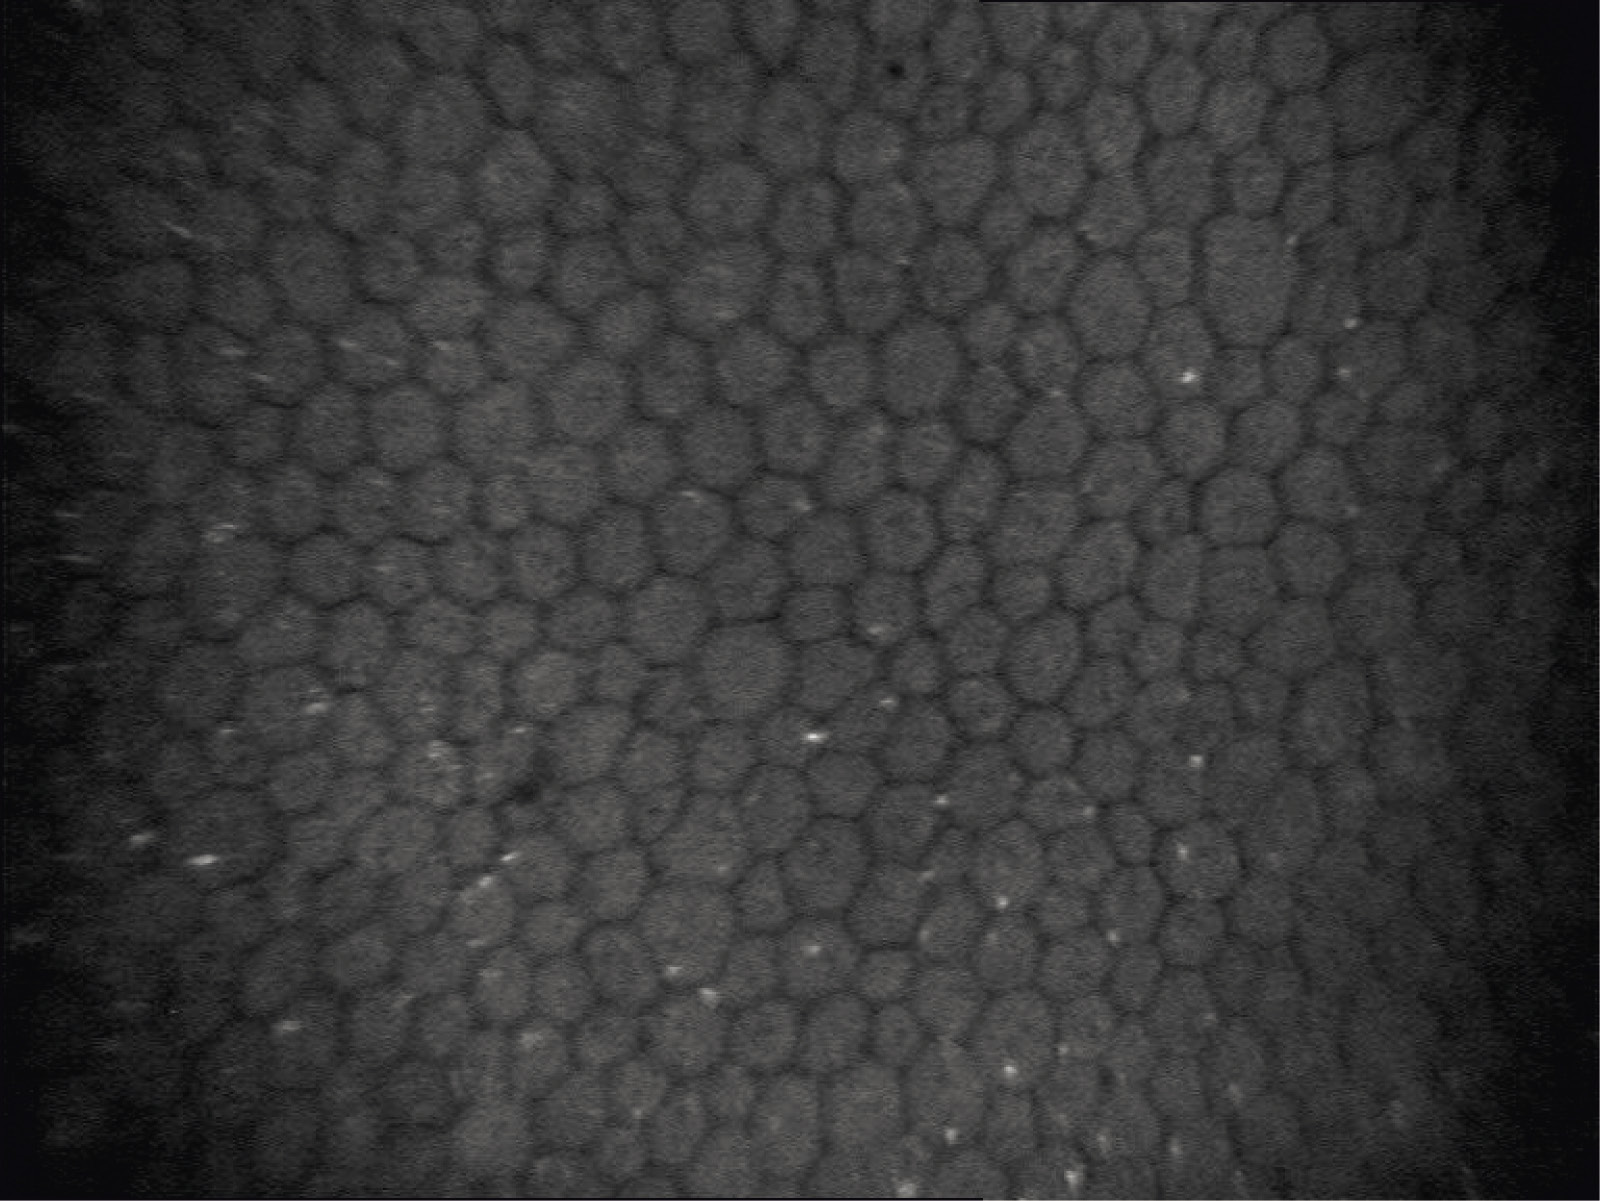

Кроме того, проводили бесконтактную конфокальную микроскопию с помощью щелевого сканирующего конфокального томографа Confoscan 4 (Nidek, Япония). Размер исследуемой области 460×690 мкм, латеральное разрешение 0,8–2,0 мкм/пиксель, размер изображения 768×576. Объектив (×20) размещали на расстоянии 12 мм от роговицы пациента. Микроскоп был выровнен и сосредоточен на центре роговицы.

Результаты конфокальной микроскопии показали более значительную потерю плотности эндотелиальных клеток (ЕCC) при ПЗУГ по сравнению с ПОУГ. Примечательно, что, в отличие от ПОУГ, при которой все показатели роговичного эндотелия возвращались к исходным спустя месяц после СЛТ, при ПЗУГ они достоверно отличались от исходных даже спустя полгода после операции. На рис. 3 заметно, что при одинаковых характеристиках эндотелия до СЛТ при обеих формах глаукомы роговичный эндотелий при ПЗУГ, в отличие от ПОУГ, остается измененным спустя полгода после операции: ECC снижена (плотность клеток роговичного эндотелия до СЛТ при ПОУГ 2473±177 и 2436±171 (р=0,180) при ПЗУГ, через 6 месяцев при ПОУГ 2467±154 (р=0,342) и 2396±170 (р=0,002) при ПЗУГ), остаются темные «пустоты», свидетельствующие о сохранении воспалительной реакции со стороны роговичного эндотелия.

ПЗУГ: пациентка 63 года, ПЗО 22,69 мм, длительность анамнеза глаукомы 4 года. ПОУГ: пациент 63 года, ПЗО 23,27 мм, длительность анамнеза глаукомы 4 года. ECC – плотность клеток роговичного эндотелия (corneal cells count)